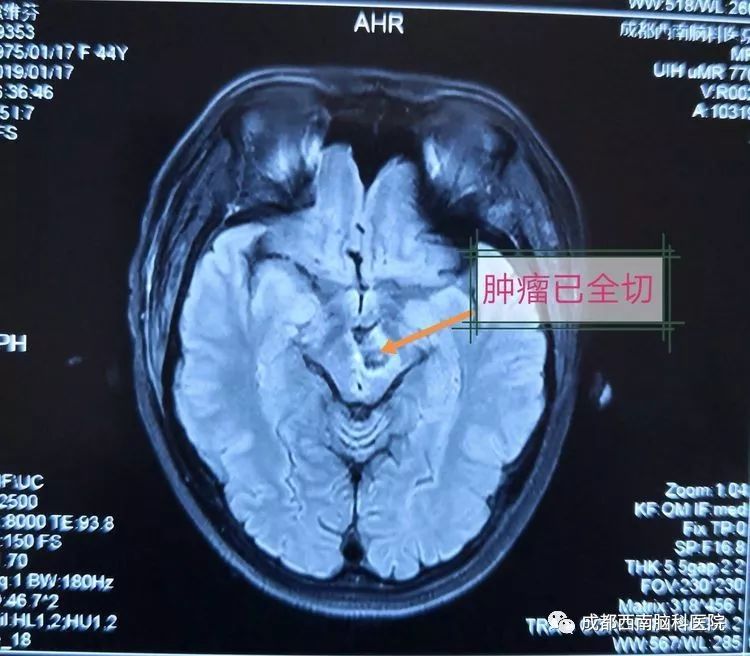

术后复查MRI显示已全部切除